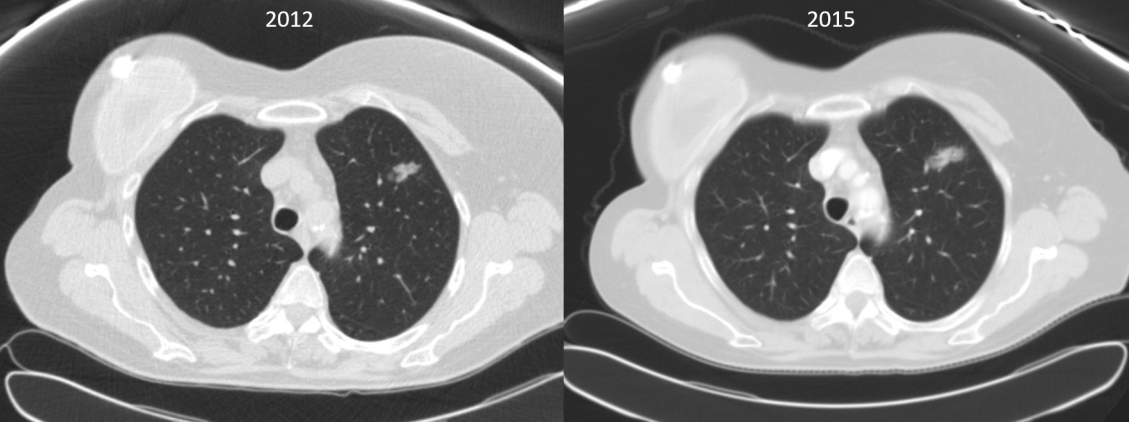

A 70-year-old woman with a past history of breast cancer in 2004 also had a nonperipheral pseudonodular ground glass appearance lesion in the left upper lobe since 2010, a core-needle biopsy in 2012 and 2015, and a diagnosis of benign pneumocytoma (Figure 1). Since 2018, the lesion had a growth of the solid component in chest computed tomography scan, so a positron emission tomography scan was performed, which showed an increased metabolic uptake in the lesion (SUV max 2.77) (Figure 2).

Figure 2